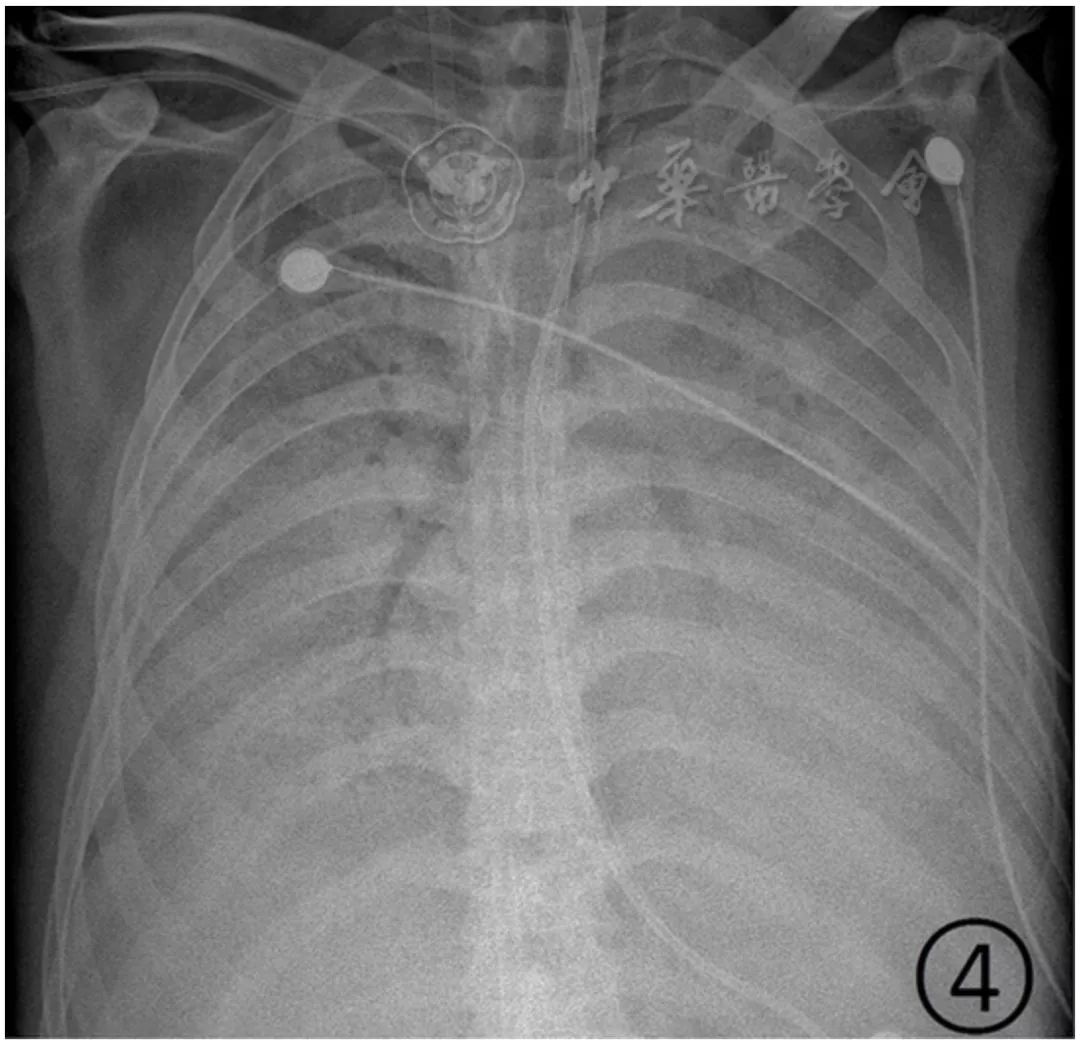

图4 男,44岁,新型冠状病毒感染的肺炎。胸部平片显示双肺弥漫性实变,肺门旁空气支气管征,呈"白肺"表现

重型患者双肺多发实变影,部分融合成大片状实变,可有少量胸腔积液(图3)。病变进展为危重型,表现为两肺弥漫性实变阴影,呈"白肺"表现(图4),可以伴有少量胸腔积液。